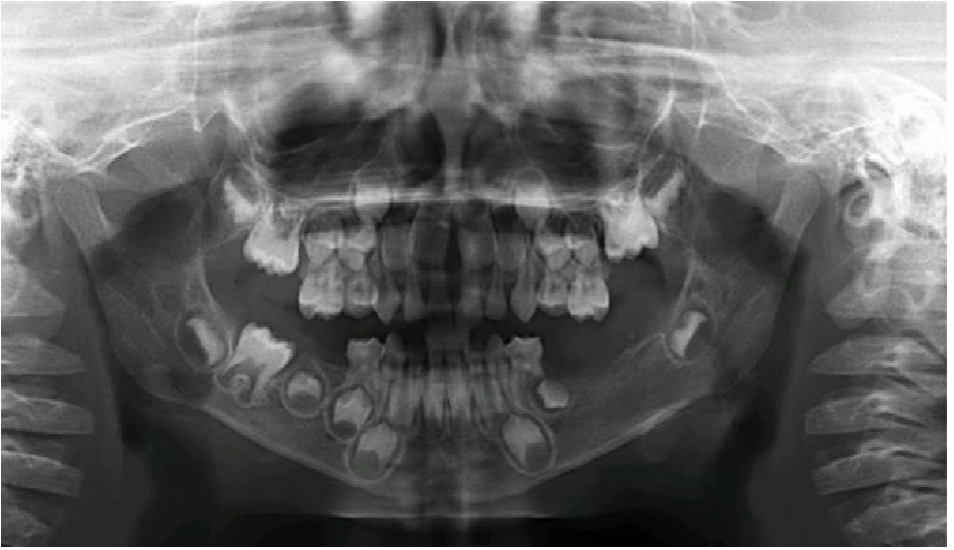

En el 2014, un dentista privado refirió a un paciente masculino de 3 años a la clínica de la Residencia de Odontopediatría de la Escuela de Medicina Dental de la Universidad de Puerto Rico, para evaluar una posible enfermedad periodontal en los segundos molares inferiores primarios1. El examen intraoral reveló una inflamación en la gingiva de los lados izquierdo y derecho, a nivel de los segundos molares inferiores primarios, obliterando el ángulo mandibular (Figura 1). Otros tejidos orales aparecieron dentro de los limites normales. En esa primera visita, luego del examen clínico, se obtuvo una radiografía panorámica la cual reveló una perdida ósea bilateral en los segundos molares primario derecho e izquierdo mandibular. La lesión del lado izquierdo mostraba un patrón radiolúcido extenso de márgenes irregulares desde el segundo molar primario hacia el folículo del primer molar permanente, desplazándolo posteriormente y creando una apariencia de dientes flotantes.1 El paciente recibió intervención quirúrgica con biopsia excisional y curetaje de las áreas afectadas con extracción de los segundos molares mandibulares primarios y el folículo del primer molar mandibular permanente izquierdo. Los especímenes obtenidos tanto del lado derecho como izquierdo mandibular fueron consistentes con Histiocitosis de Células de Langerhans. Posterior a este diagnóstico, el paciente fue referido al servicio de hematología/oncología para evaluación y tratamiento. Una tomografía computarizada fue ordenada la cual reveló que también había lesiones menores en el hígado y el área abdominal. El paciente fue tratado posteriormente con quimioterapia. Durante 3 años, el paciente continuó un protocolo riguroso de seguimientos dentales cada 3 meses con un dentista pediátrico y cada 6 meses con una cirujana maxilofacial. En el 2017, el seguimiento reveló en la radiografía panorámica y radiografía de mordida, una radio lucidez periapical del primer molar primario izquierdo envolviendo el primer premolar permanente. Debido al historial previo se tomó la decisión de realizar una segunda intervención en sala de operaciones donde se extrajeron el primer molar primario izquierdo y el folículo del primer premolar permanente izquierdo. El resultado de esa biopsia reveló un folículo dental agrandado y células inflamatorias sin evidencia de recurrencia de la lesión previa. En seguimiento, el paciente ha presentado exámenes clínicos y radiográficos periódicos sin evidencia de lesiones recurrentes. En el último seguimiento en el 2019, no reveló nuevas lesiones y el paciente se encontraba asintomático. La Figura 2, resume la toma de radiografías panorámicas durante el periodo de 2014 a 2019.

Radiografía panorámica (2014). Paciente de 3 años, con lesión radiolúcida extensa del cuerpo mandibular izquierdo envolviendo el segundo molar primario izquierdo y el folículo del primer molar permanente izquierdo con desplazamiento del mismo.